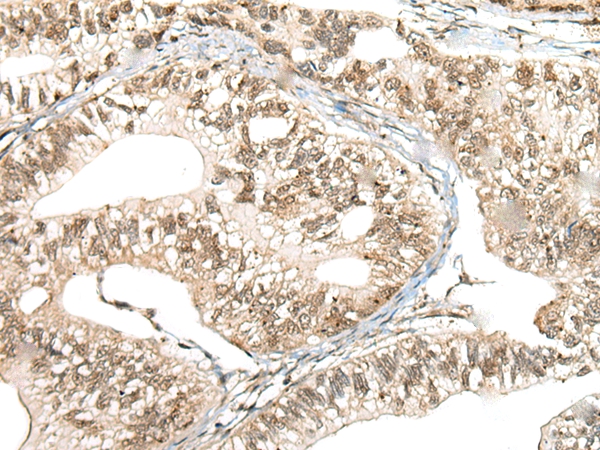

The image on the left is immunohistochemistry of paraffin-embedded Human gastric cancer tissue using 46427(CCNK Antibody) at dilution 1/40, on the right is treated with fusion protein. (Original magnification: x200)

The image on the left is immunohistochemistry of paraffin-embedded Human thyroid cancer tissue using 46427(CCNK Antibody) at dilution 1/40, on the right is treated with fusion protein. (Original magnification: x200)